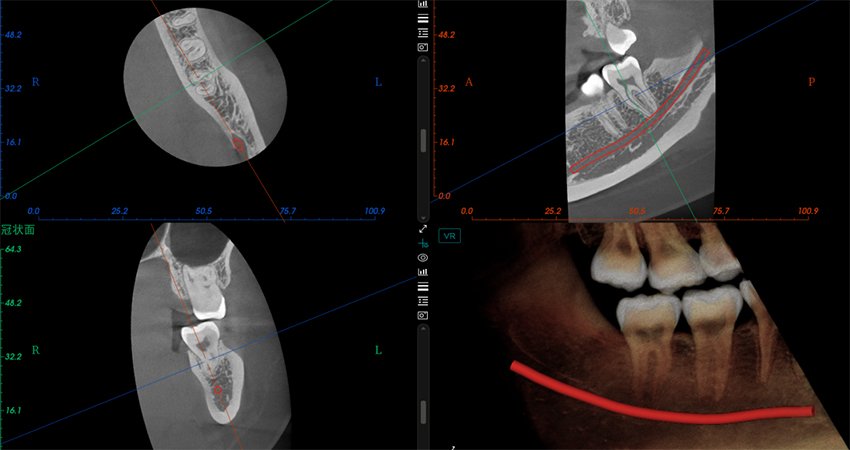

El software de diagnóstico 3D líder de Meyer y el sistema de análisis ortodóntico inteligente adoptan un diseño de UI modular, lo que hace que las funciones del software sean más cercanas a las necesidades clínicas y más fáciles de usar para los médicos, reduciendo significativamente el costo de aprendizaje.

Software de Diagnóstico 3D

MyDentViewer